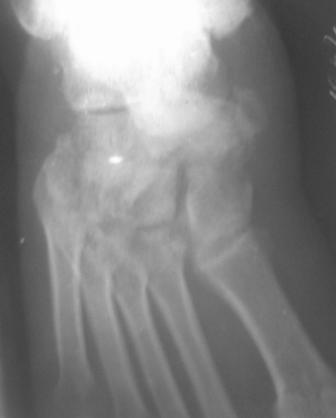

По данному случаю, оказалось 3 месяца назад было произведена Р-графия в райбольнице, но больной предпочел лечится у табиба. Присылаю первичные снимки.

Да, наш с Вами диагноз, Абдурашид, подтвердился. Я бы предпочёл артродез, фиксация- в самом простом варианте-винтами 3,5 или 4,5 . Отломок послужит аутотрансплантатом. Плюс внешняя иммобилизация. С уважением, Волна